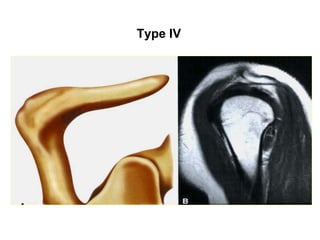

MOÛM CUØNG VAI

Type I

Type II

Type III

Type IV

Moûm cuøng vai vò trí bình thöôøng

Moûm cuøng vai doác xuoáng

(downsloping)

Mỏm cuøng vai nghieâng xuoáng döôùi ngoaøi

(inferolateral tilt)

Moûm cuøng vai naèm thaáp (low-lying)